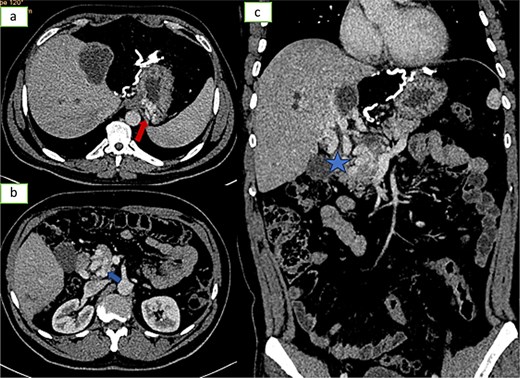

![Axial sections of an injected abdominopelvic CT scan [(a) arterial temp; (b) portal temp] and (c) coronal reconstruction showing portal hydatidosis with the presence of a cavernoma of the hepatic hilum.](https://oupdevcdn.silverchair-staging.com/oup/backfile/Content_public/Journal/jscr/2025/5/10.1093_jscr_rjaf337/1/m_rjaf337f3.jpeg?Expires=1778282696&Signature=WZSVNjAljj9A2J4gwzBvEgWhbngdokVsEzYzgcn~BzYJiNiaexv-lQQaVqBFL7fMppyToj0n16kgYA8ZpvQYQ8QR4WYeWoKagXCx~VcnLCsckuN4obar4k9ul5hZb3slXUxW9q0CeUc3VstGsGQZgauxcJ37cS~cY3y~wlZ6wyB0JlU~8ItzS7nBLU~mLtMCmYajNLIjgXeU9ANvCvPNzcmoHxoS3SNk0ALWODB-w6QP9h4~5h7ZyDE30vqVTxLmqrxdBQl6qrwWdxPmgCnQ1y8puu2kzml3L5e0BTM6xsNZUhyuWrvgX-yHsIabyIGzuEHOnX5-iU9hSEWjr4FRPQ__&Key-Pair-Id=APKAIYYTVHKX7JZB5EAA)

Axial sections of an injected abdominopelvic CT scan [(a) arterial temp; (b) portal temp] and (c) coronal reconstruction showing portal hydatidosis with the presence of a cavernoma of the hepatic hilum.

Axial sections (a and b) and coronal reconstruction (c) of an injected abdominopelvic scan showing signs of portal hypertension: gastric varices, peripancreatic varices.